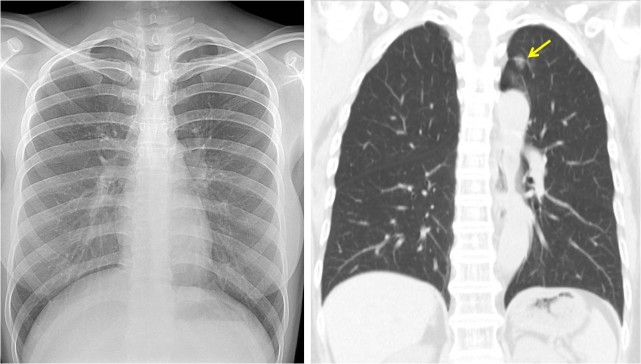

图片(患者的CT与磁共振结果,红框内为可疑结节)

这位肠癌患者在做术前CT分期时,在肝脏上看到了两枚模糊的结节,这个时候是要考虑肝转移的,但是因为CT的软组织分辨率有限,对于一些不典型转移和良性病灶鉴别起来比较困难。而该病例如果确定肝转移,治疗选择就会不一样,可能会从直接手术转为先化疗再手术。

所以我们在MDT(多学科诊疗)讨论后建议先进行MRI(磁共振)检查进一步确认。MRI软组织分辨率优于CT,对肝转移鉴别的准确率更高。后来这位患者做了MRI后发现,肝脏结节是一个典型肝血管瘤的表现,而肝血管瘤是良性肿瘤,这么小是不需要任何处理的。后来患者放心进行了肠癌手术,至今生存超过五年没有复发。

至于具体要筛查哪些项目,要根据患者的年龄、肿瘤家族史,有没有吸烟、酗酒等高危因素来进行判断。涉及到影像学的筛查手段,包括腹部、甲状腺和妇科的肿瘤可以用B超来做初筛初诊,肺癌适合用低剂量螺旋CT来初筛,肺的早癌拍胸部X线平片是很难看出来的。美国有一组数据,比较通过X线胸片体检和用低剂量螺旋CT体检的结果,后者能够把肺癌死亡率降低五分之一,这是非常大的一个提高了。所以,肺癌筛查要用低剂量螺旋CT。

图片(左图为X线胸片,未见异常征象;右图为肺CT,可见左上肺结节,手术证实为周围型肺腺癌)